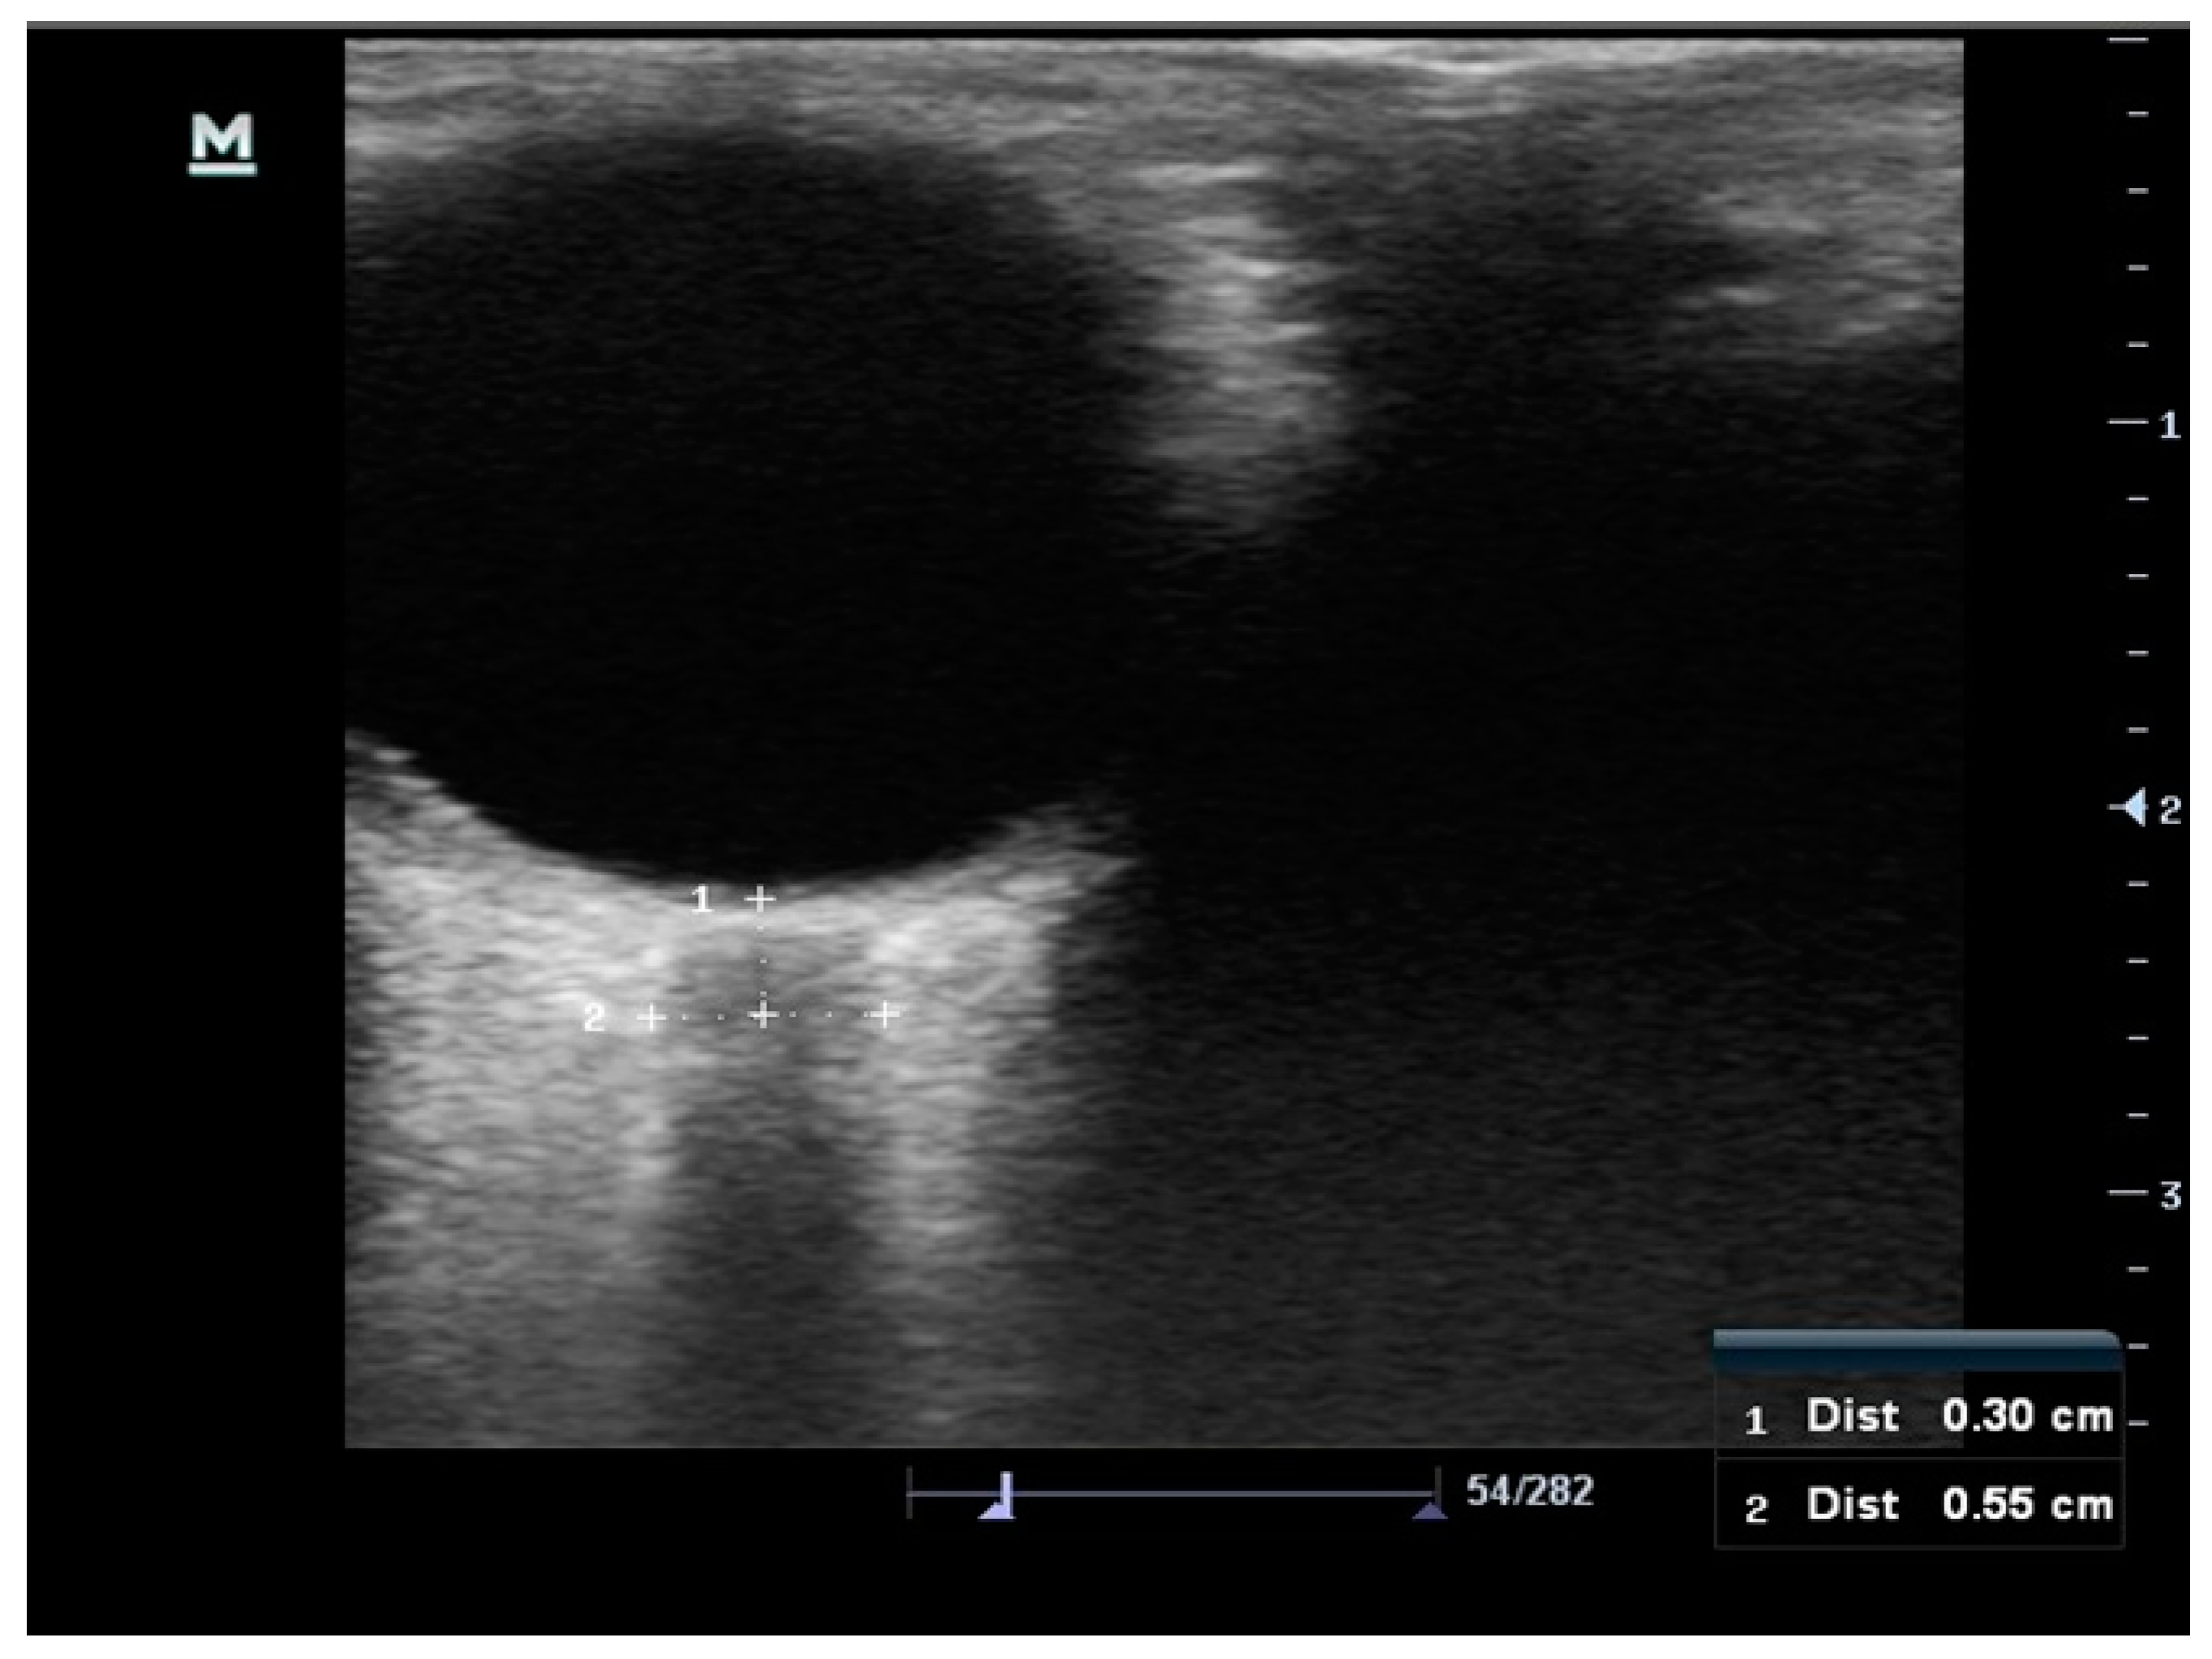

2.1. Measurement of the Optic Nerve Sheath Diameter